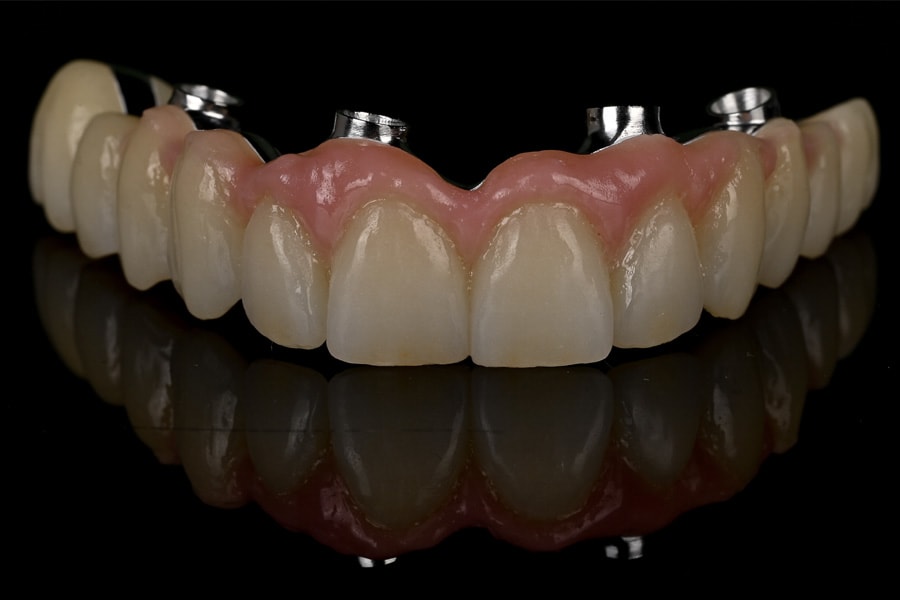

Definitive frameworks were CAD-designed and CNC-milled from titanium alloy (Figure 22). Clinical fit was confirmed with the Sheffield test (Figure 23). Monolithic zirconia superstructures were produced and vestibularly veneered with feldspathic ceramics to enhance translucency and texture (Figure 24 and Figure 25). Selective pink ceramic was applied in gingival areas requiring soft-tissue compensation (Figure 26 and Figure 27).

Occlusion was once again validated using jaw-motion tracking, confirming harmony with functional dynamics (Figure 28). The definitive prostheses were delivered as screw-retained restorations, achieving esthetic integration, functional stability, and patient satisfaction (Figure 29 and Figure 30).